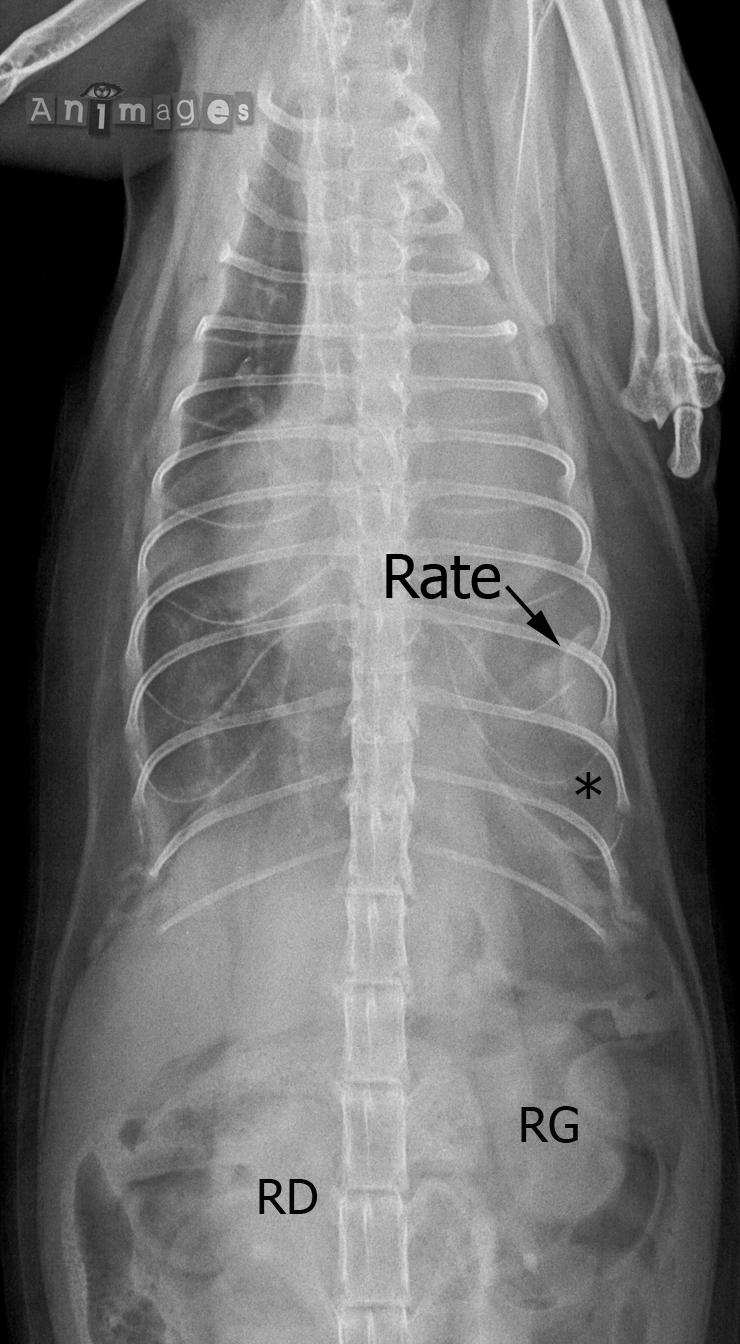

VD